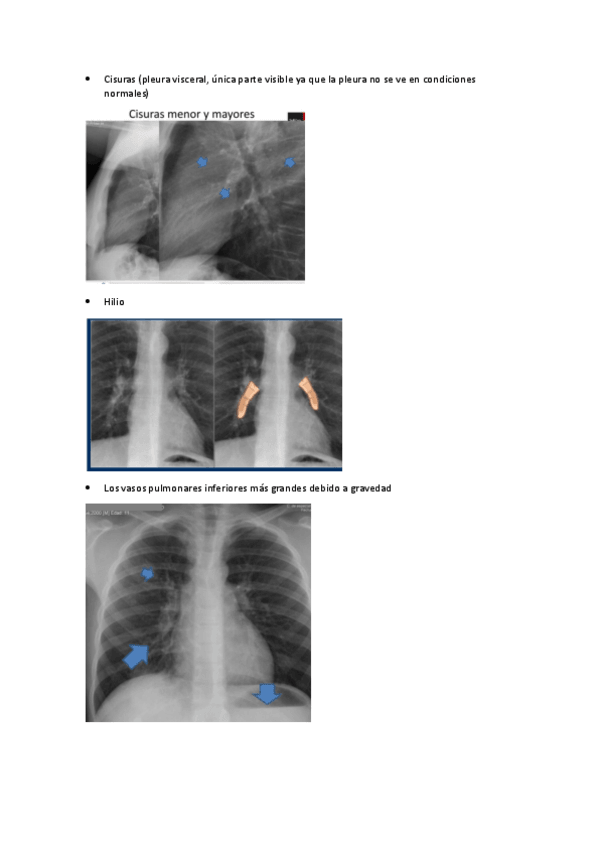

Tema-7-anatomia-radiologica-del-torax.pdf

Tema-7.-Anatomia-radiologica-torax.pdf